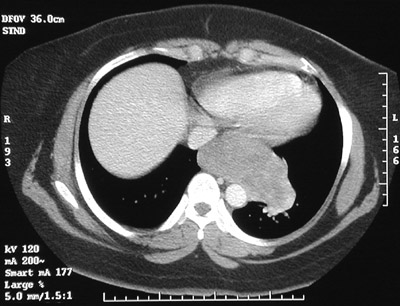

| There is a large mass involving the lower esophagus and extending to the upper gastric fundus in these abdominal CT scan views in the lower chest above and upper abdomen below. This is a gastrointestinal stromal tumor (GIST). These tumors are composed of spindle cells. The biologic behaviour is unpredictable. |